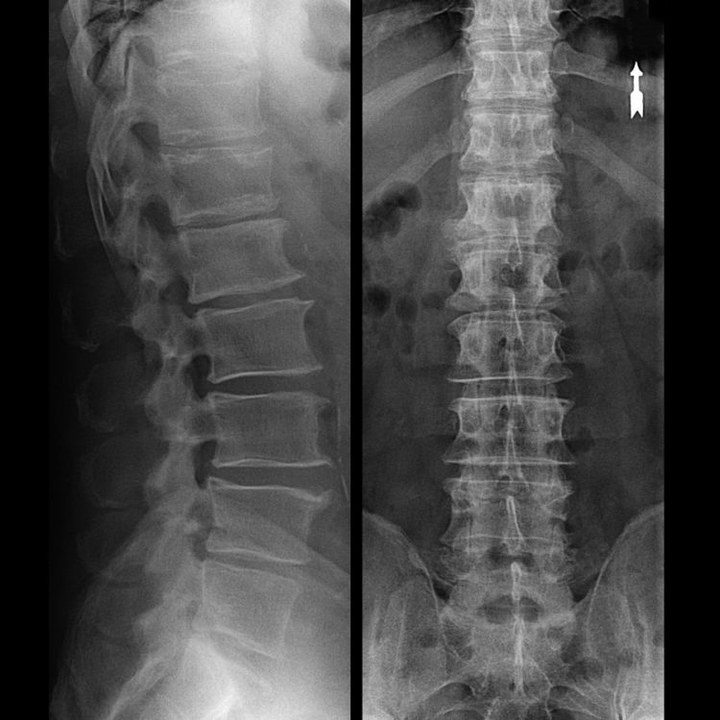

Tüüpilistel juhtudel esineb emakakaela ja emakakaela-rindkere lülisamba osteokondroos ülalkirjeldatud viisil. Seetõttu oli ja jääb diagnoosimise peamiseks etapiks patsiendi kaebuste tuvastamine, samaaegse lihasspasmi olemasolu kindlakstegemine, kasutades lülisamba lihaste lihtsat palpatsiooni. Kas röntgenuuringu abil on võimalik osteokondroosi diagnoosi kinnitada?

Emakakaela lülisamba "röntgeniülesvõte" ja isegi painde ja sirutuse funktsionaalsete testidega ei näita kõhre, kuna nende kude edastab röntgenikiirgust. Sellele vaatamata saab selgroolülide asukoha põhjal teha üldisi järeldusi lülivaheketaste kõrguse, kaela füsioloogilise kõveruse üldise sirgendamise - lordoosi kohta, aga ka marginaalsete kasvude esinemise kohta selgroolülidel koos nende pindade pikaajalise ärritusega habraste ja dehüdreeritud lülivaheketaste poolt. Funktsionaalsed testid võivad kinnitada emakakaela lülisamba ebastabiilsuse diagnoosi.

Kuna kettaid endid saab näha ainult CT või MRI abil, on kõhre ja moodustiste, nagu eendid ja herniad, sisemise struktuuri selgitamiseks ette nähtud magnetresonants- ja röntgen-kompuutertomograafia. Seega tehakse nende meetodite abil täpselt diagnoos ning tomograafia tulemus on näidustus ja isegi aktuaalne juhend hernia kirurgiliseks raviks neurokirurgia osakonnas.